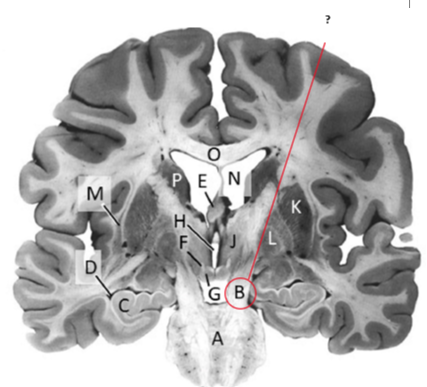

Name this and state its function. And what tract is involved?

Mamillary bodies.

Name this ,state its function and the name of the structures closely associated with it.

Putamen.

Name this, state its function and its components[4 marks].

Globus Pallidus.

Components: